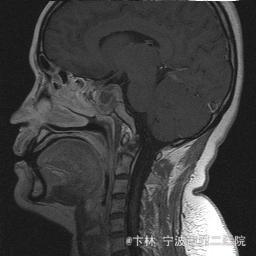

40岁女性,因“双眼视力下降三月余伴停经1个月余”入院。 患者三月前无明显诱因下出现双眼视力下降,视物模糊,尤以左眼为甚,只能近距离看到手动,无头痛、头晕,无恶心、呕吐,无视物旋转,无行走困难等不适,患者曾在某眼科医院就诊治疗,考虑为双眼视神经炎,予以营养,补液对症等治疗(具体不详),情况不见好转,近一月来患者月经停止,来我院神经外科门诊,予以查头颅CT,头颅MRI,提示“垂体大腺瘤”,为求进一步治疗收住入院

予以完善血,尿,粪常规检查,及凝血功能全套,输血功能全套及垂体功能全套,蝶鞍冠状CT等术前检查措施,行经蝶入路垂体瘤切除术。术后予以对症,补液,调节血电解质等治疗,患者视力明显改善,复查头颅MRI提示肿瘤基本全切,一周后患者出院。

此病人颅内垂体瘤体积较大,突破鞍隔压迫视交叉,故患者视力视野障碍为首发症状,该肿瘤主体有大部分向蝶窦腔生长,因此采用经蝶手术入路,肿瘤切除满意,术后患者视力视野恢复满意,。